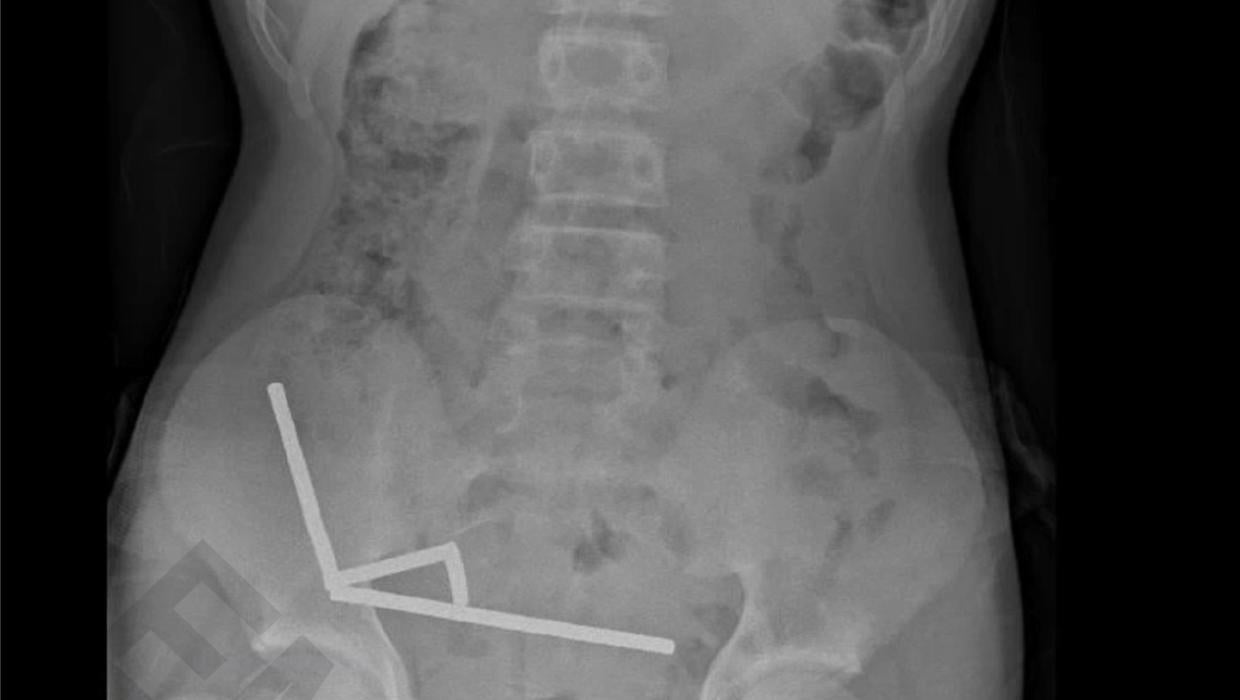

A 13-year-old boy required urgent surgery at Tauranga Hospital in New Zealand after swallowing nearly 100 magnets. The situation escalated quickly, necessitating a significant surgical intervention that involved the removal of part of his bowel.

The incident occurred when the boy ingested multiple small magnetic objects, which posed serious health risks. Medical experts warn that swallowing such items can lead to severe complications, including intestinal blockage and perforation. In this case, the magnets attracted each other within the boy’s digestive system, creating a chain reaction that caused significant damage.

Dr. Andrew Wills, a member of the medical team at Tauranga Hospital, described the procedure as a “major surgery.” He emphasized the urgency of the situation, stating that timely intervention was crucial to prevent further health complications. The surgical team worked meticulously to address the internal injuries caused by the magnets.